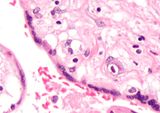

Micrograph of a cytomegalovirus (CMV) infection of the placenta (CMV placentitis). The characteristic large nucleus of a CMV infected cell is seen off-centre at the bottom-right of the image. H&E stain.